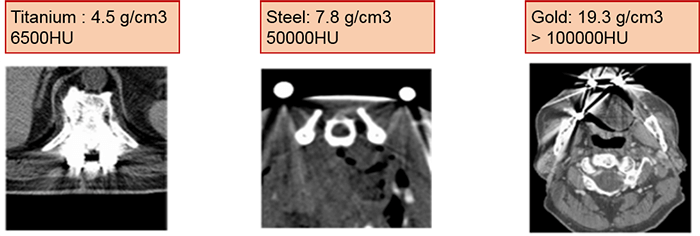

The formation of these artifacts is due to the impossibility of algorithms to take into consideration the very high-density values. This causes misinterpretation of images as the metals absorb more of the x-rays. This absorption creates shadows.

Compare the density of the prosthetic materials in these images all taken at 120 kV. As you can see, gold has the highest Hounsfield units.